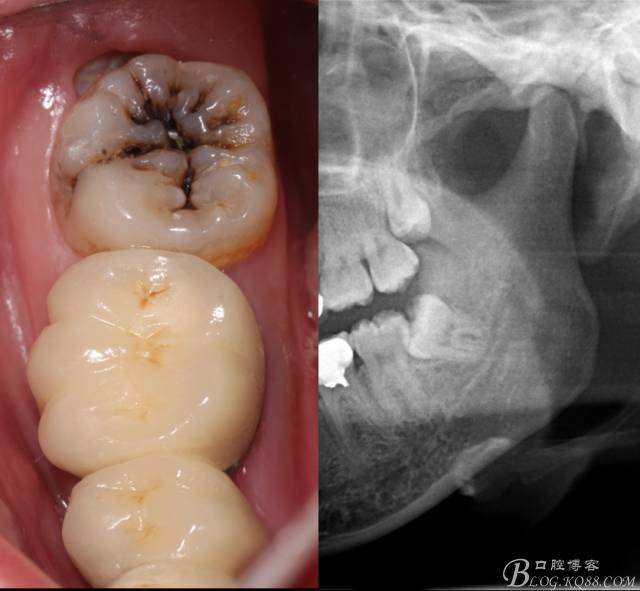

檢查:(1)37牙合面齲,卡探針.         (2)38近中埋伏阻生

X全景片示38近中三類阻生,非融合根,近中根壓下頜管,37遠(yuǎn)中鄰面中齲樣影像。

診斷:(1)37中齲        (2)38近中阻生

治療建議:37齲修復(fù)后撥除38.

先分析智齒的情況,口內(nèi)直觀是半個(gè)牙尖都沒露出來,差一點(diǎn)就完全埋伏了。磨牙后墊的可操作面積中規(guī)中紀(jì),X全景片示三類阻生,根冠比例是1:1,非融合根,近中根壓下頜管。